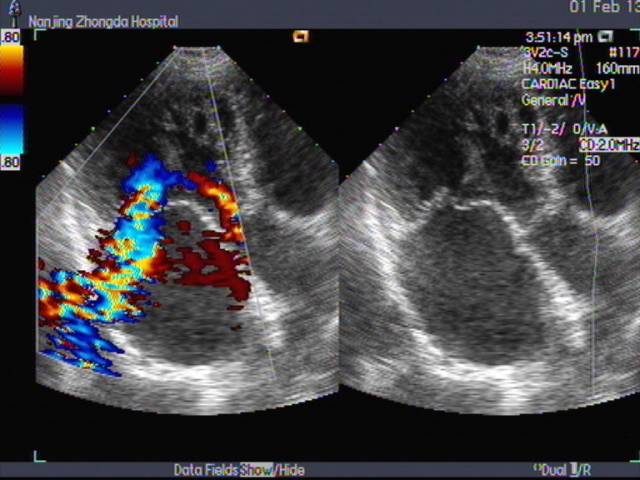

心超(2013-02-01)LA 5.3 RA 4.6 RV 2.7 LV 5.6 LVEF 0.60 TR 3.4(PG=45mmHg)二尖瓣前叶脱垂伴中-重度关闭不全 左心房、右心房、左心室扩大 主动脉瓣钙伴轻中度关闭不全 三尖瓣中度关闭不全 肺动脉高压。